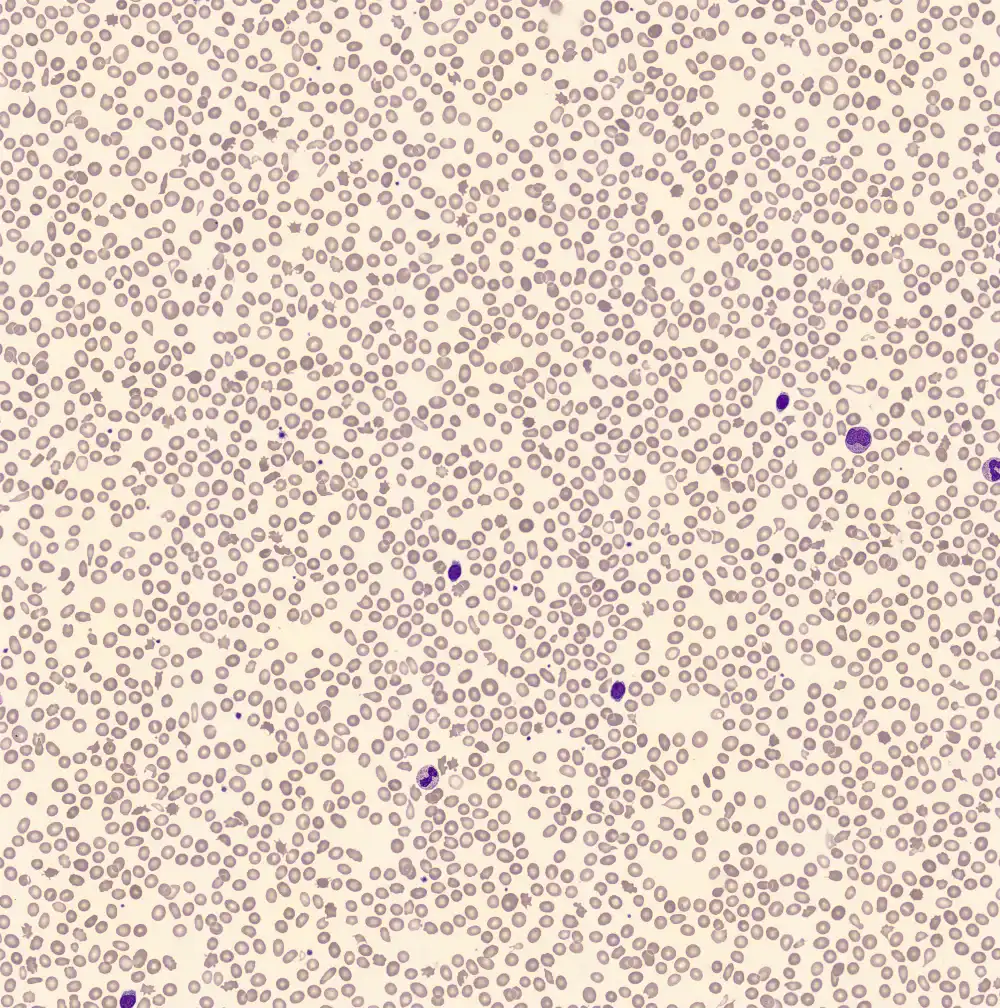

Doornappelcellen zijn erytrocyten met meerdere uitsteeksels door verstoring van de celmembraan. Formeel wordt er onderscheid gemaakt tussen echinocyten (10-30 regelmatige uitsteeksels) en acanthocyten (<20 onregelmatige, puntige uitsteeksels), maar dit is in de praktijk vaak erg moeilijk. Hun etiologie is echter anders.

Acanthocyten ontstaan door een verhoogde opname van cholesterol in het membraan, wat gezien kan worden bij een verstoorde

lipide stofwisseling door bijvoorbeeld leverziekte. Echinocyten kunnen ontstaan bij het te langzaam drogen van een bloeduitstrijkje, langdurige blootstelling aan EDTA (artefact) of door een fysiologische verstoring van de osmotische gradiënt (en daarmee relatieve uitdroging van de erytrocyt).